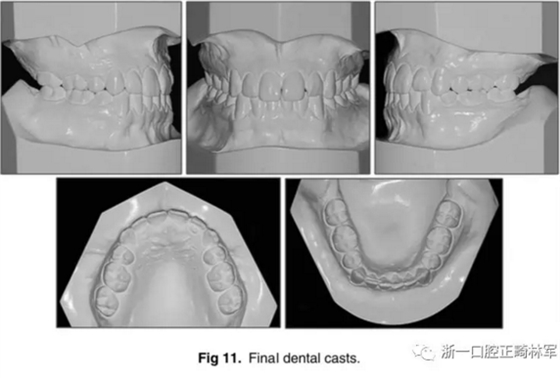

口內(nèi)相及模型:雙側(cè)磨牙、尖牙I類關(guān)系,良好的牙尖交錯關(guān)系,覆合、覆蓋正常。

影像學(xué):全景片示:牙根平行度可。頭顱側(cè)位片及疊加圖示:顯著的骨性、牙性改變;其中,最大的改變?yōu)樯舷骂M位置關(guān)系,改變了7mm;由此帶來的改變?yōu)锳NB角從-4°變?yōu)?°,Wits值由-10mm變?yōu)?1.5mm,上頜突度減?。ˋ-NPer,3mm),上下頜不調(diào)改善(Co-A-Co-Gn,41mm),從而使側(cè)貌更為平直;下頜磨牙遠(yuǎn)中移動,無伸長、傾斜,反映了下頜整體的遠(yuǎn)中移動;上下切牙傾角糾正(1:NA,7mm、25°; 1:NB,4.5mm、20°; IMPA,78°),從而改善了在基骨中的位置。

功能:前伸合的切牙引導(dǎo)與側(cè)方合的尖牙引導(dǎo)得以實(shí)現(xiàn)。

側(cè)貌:上唇突度增大4mm(至S線0mm),整體側(cè)貌更為和諧。

5年隨訪:治療結(jié)果保持穩(wěn)定,無明顯復(fù)發(fā),但下頜中線有輕微偏移;下頜磨牙位置始終保持穩(wěn)定。